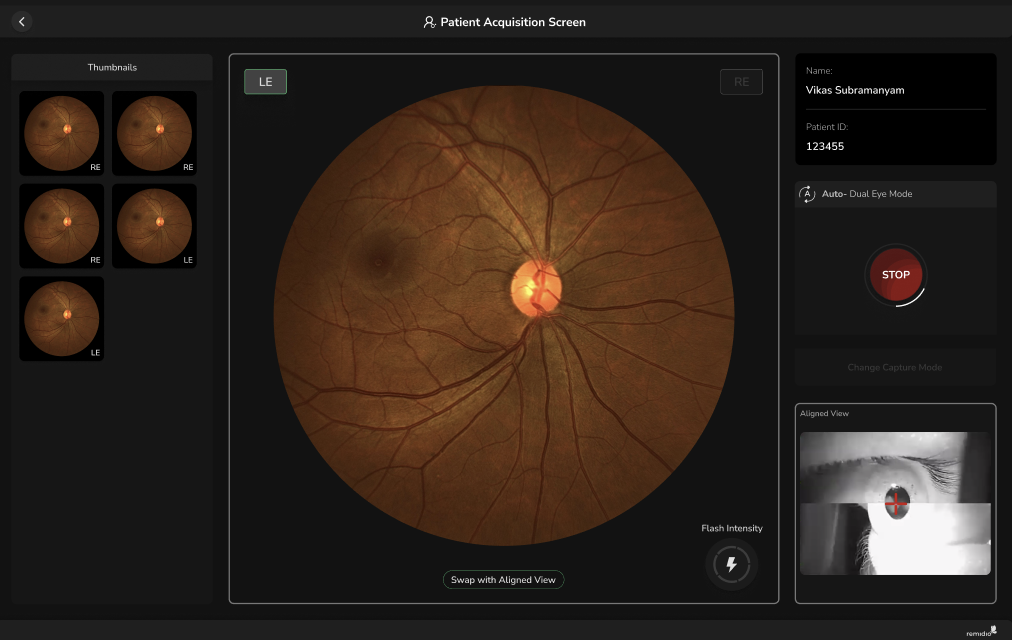

Laser autofocus, auto-pupil tracking and two different image modalities ensuring faster capture

Laser autofocus, auto-pupil tracking and two different image modalities ensuring faster capture

Designed for fast, high-volume screening

Automated image acquisition enables rapid retinal imaging with minimal training and reduced operator dependence

Just hold the device in place and choose an eye segment. The FOP will automatically capture an image for you - its as easy as that.